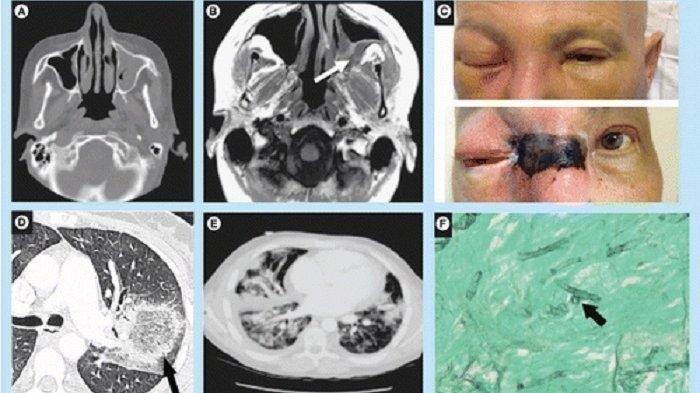

futuremedicine.com

Mucormycosis yang sangat agresif dan mematikan.

Gejala pertama kali bermanifestasi sebagai infeksi sinus, demam, dan sakit kepala.

Namun, jika infeksinya menyebar, dapat menyebabkan hilangnya jaringan di langit-langit mulut, septum, hidung, dan mata.